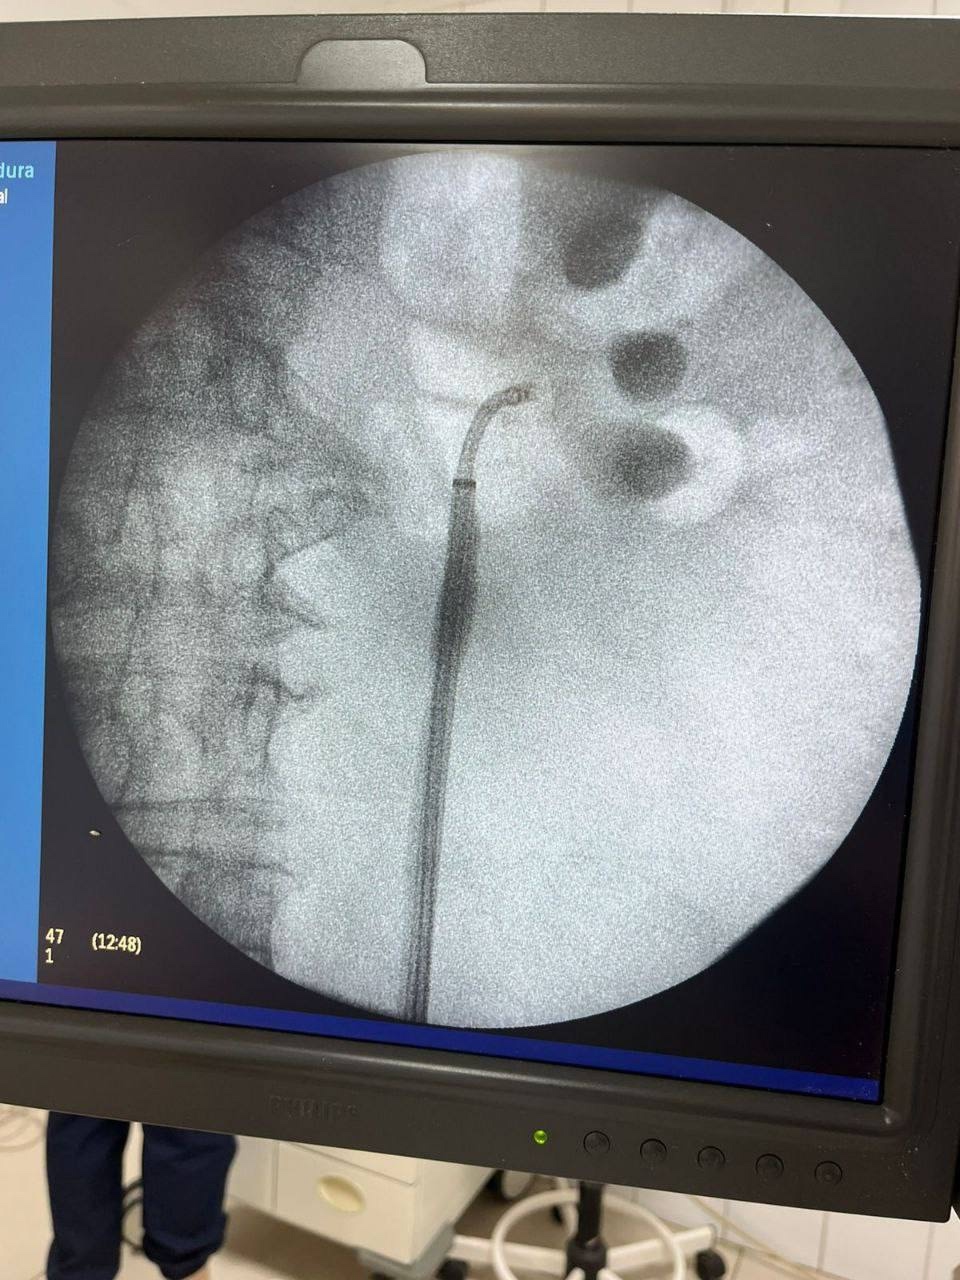

По словам заведующего отделением, операция была проведена возрастной пациентке с избыточной массой тела, у которой диагностировали «вколоченный» камень мочеточника, блокаду левой почки и стриктуру лоханочно-мочеточникового сегмента (ЛМС – сужение участка, где почка соединяется с мочеточником), вызванную длительным стоянием конкремента. Классическая ригидная уретероскопия в данном случае оказалась малоэффективной – из-за изгибов и выраженного сужения мочеточника камень не удалось визуализировать.

Использование гибкого фиброуретроскопа, инструмента с подвижным кончиком и камерой, позволило специалистам добраться до камня и точно направить лазер к любой его части. Благодаря установке мочеточникового кожуха (трубки для облегчения доступа инструментов) и активной ирригации, все фрагменты раздробленного камня были эффективно выведены наружу. Операция прошла успешно и с минимальной травматичностью для пациентки.